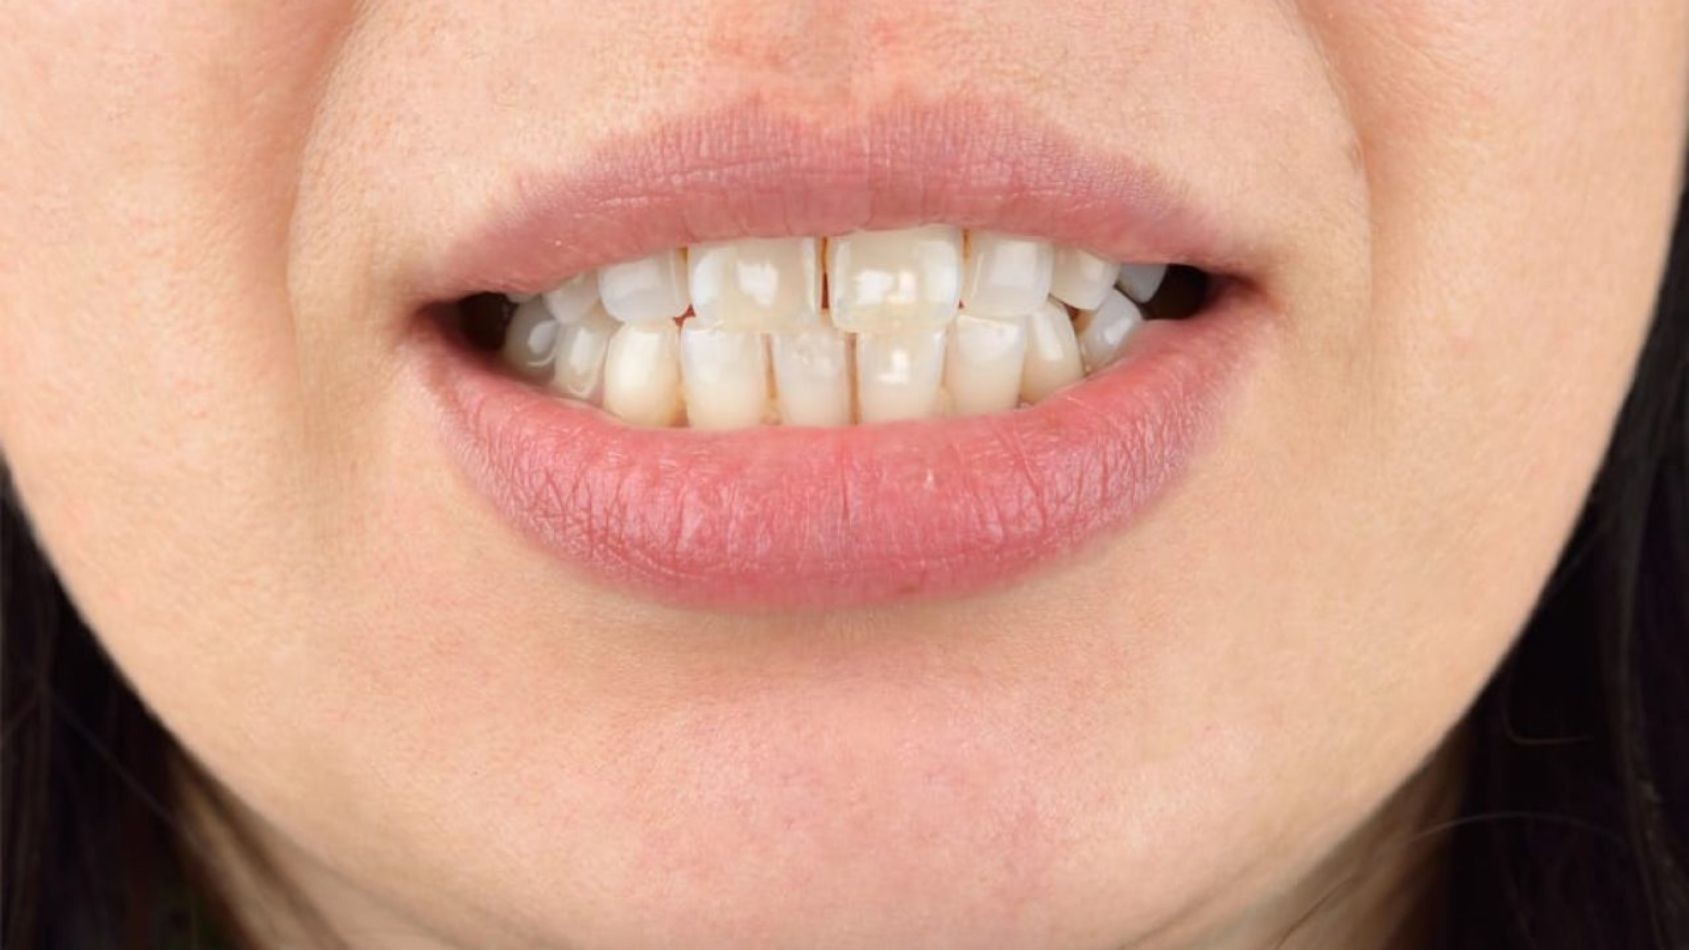

Exposing teeth to excessive fluoride alters calcium signaling, mitochondrial function, and gene expression in the cells forming tooth enamel -- a novel explanation for how dental fluorosis, a condition caused by overexposure to fluoride during childhood, arises. The study, led by researchers at NYU College of Dentistry, is published in Science Signaling.

While low levels of fluoride help strengthen and protect tooth enamel, too much fluoride can cause dental fluorosis -- a discoloration of teeth, usually with opaque white marks, lines, or mottled enamel and poor mineralization. Dental fluorosis occurs when children between birth and around nine years of age are exposed to high levels fluoride during this critical window when their teeth are forming, and can actually increase their risk of tooth decay. A survey by the CDC found that roughly 25 percent of the U.S. population examined (ages 6 to 49) show some degree of dental fluorosis.